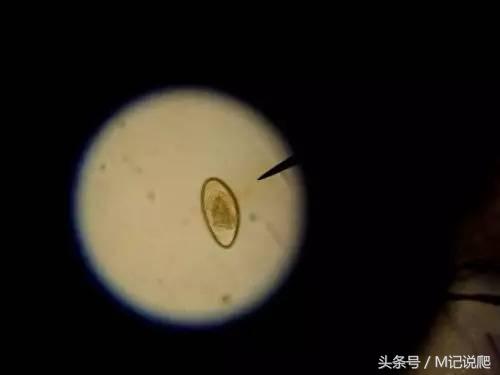

在条件允许下,最好是能先诊断是什么类型的寄生虫,再选择对应的驱虫药物,这样能提高治愈率,借助镜检技术辨别寄生虫类型是比较精准的手段。

▲显微镜下的蛲虫卵(蛲虫是线虫属下的一种寄生虫)

如果找不到镜检机构,一般肉眼能见到的虫子,基本是线虫类的。